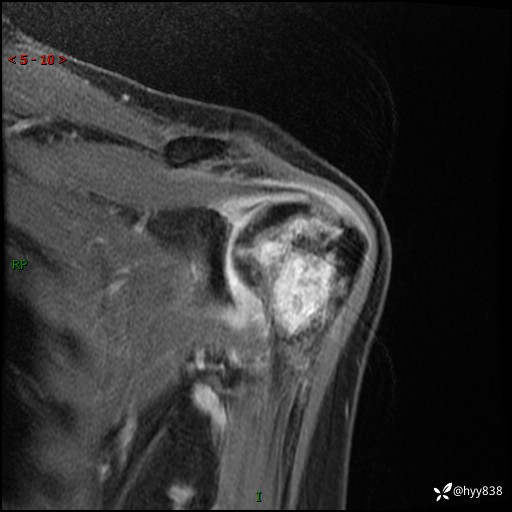

肱骨MRI平扫(axi T1WI+cor T2WI-fs)+CE-fs(COR+SAG)